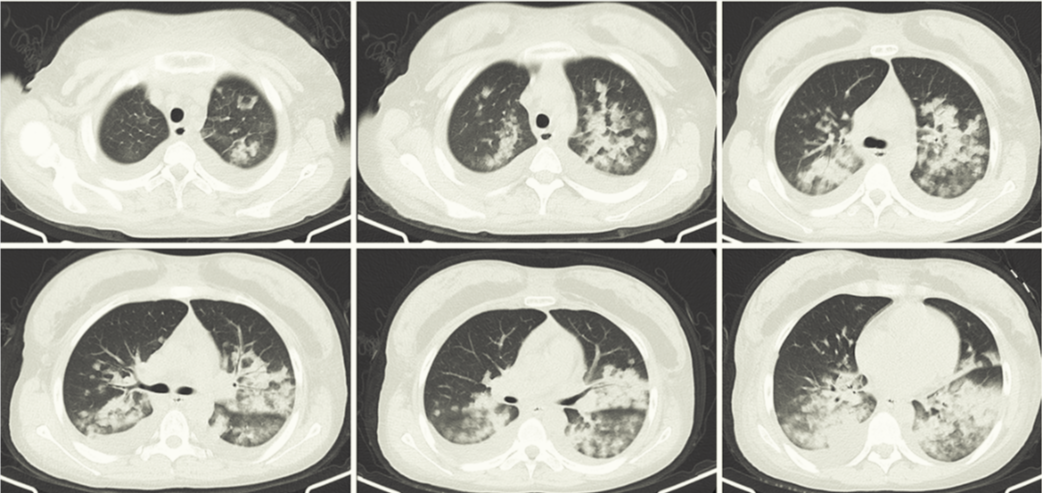

Клинический пример: пациентка через несколько часов после липосакции пожаловалась на одышку и учащение пульса.

Объективно: резкое падение сатурации (менее 80%), субфебрильная температура, кашель без мокроты. Учитывая высокий риск по жировой эмболии, была экстренно переведена в ОРИТ на неинвазивную ИВЛ с последующим бронхоальвеолярным лаважем и цитологическим изучением аспирированных клеток, где были выявлены липидные включения ("Rare case of pulmonary fat embolism and acute respiratory distress syndrome after liposuction", Gai Xiaoyan).

На серии аксиальных срезов МСКТ органов грудной полости в нативную фазу исследования определяется двустороннее снижение пневматизации легочной паренхимы в виде уплотнения по типу консолидации, а также очагов в виде "матового стекла" (морфологически соответствуют альвеолярному отеку легких), двусторонний плевральный выпот

Конкретно в данном случае была своевременно начата поддерживающая терапия и ИВЛ с благоприятным исходом в итоге.